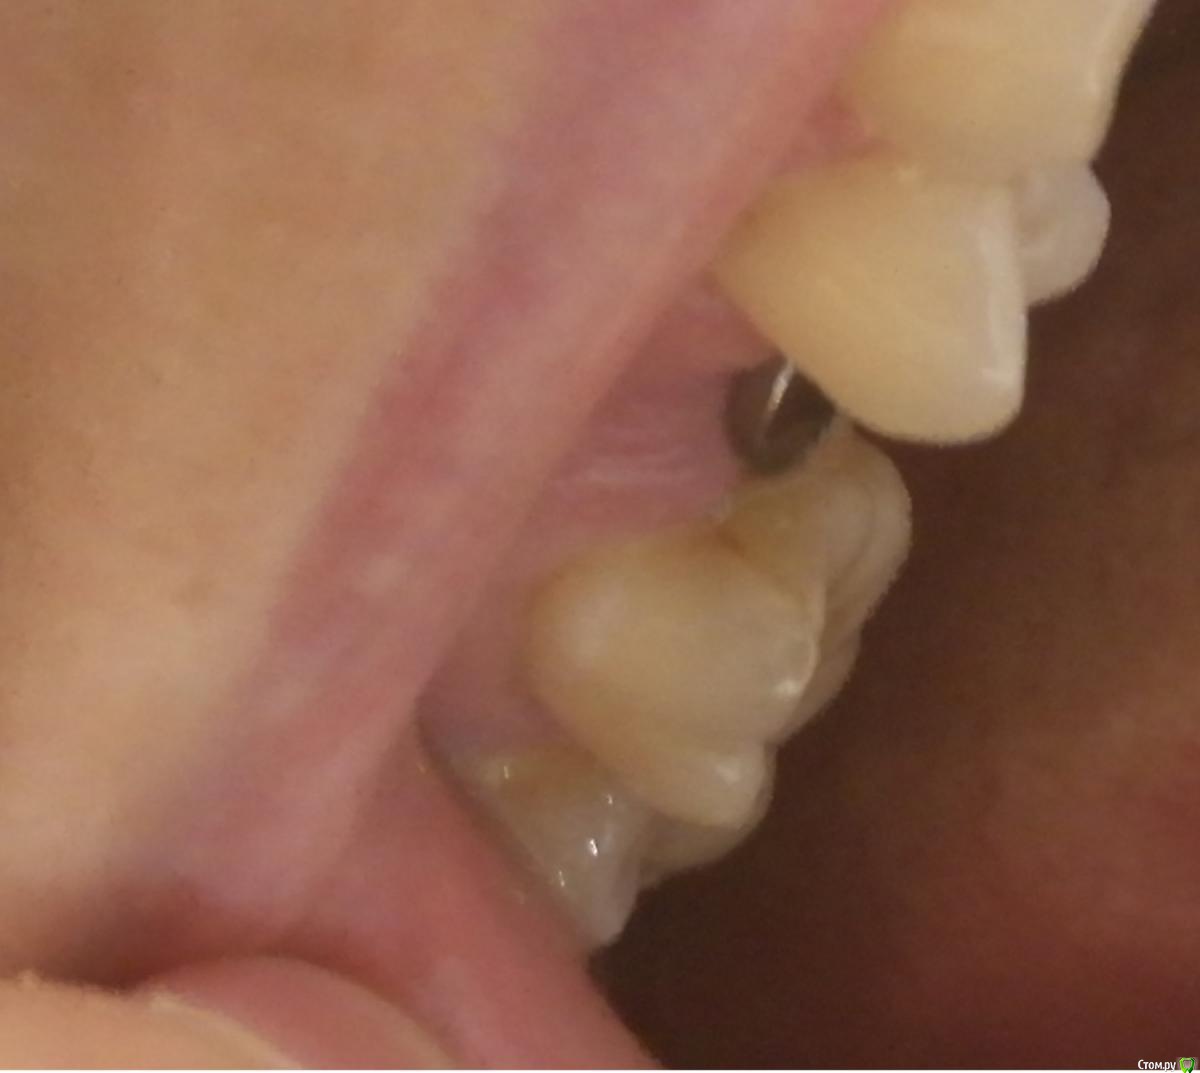

Dashik Опубликовано 1 октября, 2019 Автор Поделиться Опубликовано 1 октября, 2019 Добрый день, уважаемые стоматологи! В воскресенье 29 Сентября установили ФДМ. Сегодня 3 день, беспокоят следующие симптомы: Язык упирается прямо на часть формирователя, вызывая огромный дискомфорт. На языке вчера было только покраснение, а сегодня отпечаток круглой формы, это место болит, как при образовании язвочек на языке при стоматите. В течение дня пытаюсь язык класть на левую часть зубов или на нижнюю челюсть, но ночью и во время еды я этот процесс контролировать не могу. В первый день этот кусочек языка даже немел, передавая боль по всей правой части лица. Из-за постоянного прикосновения языка с металлом появился привкус металла во рту, особенно обостряется после питья простой воды и еды (в связи с этим стараюсь особо ничего не есть). Общее самочувствие не очень, первая ночь была бессонной из-за сильной боли в челюсти, врачу пришлось потрудиться в выкручивании заглушки. Сначала хотел даже без анестезии выкручивать, да не тут-то было. Таблетки не принимаю, предписаний никаких не было. Вчера и сегодня постельный режим. Боли перешли на тянущие, ноет вся правая часть лица. Можно ли что-то сделать с этим дискомфортом, чтобы больше не натирало язык? Или, стиснув зубы, терпеть боль до начала протезирования? Нужен ли мне вообще теперь формирователь, после того, как я отходила с заглушкой 5 месяцев? И почему он так неровно стоит, разве он не должен быть как-то посередине и не мешать естественному положению языка? Да и вообще, десна вещь капризная, нарастет ли там теперь спустя столько времени? Ссылка на комментарий

Irouil Опубликовано 1 октября, 2019 Поделиться Опубликовано 1 октября, 2019 Судя по снимкам, формирователь с небной стороны расположен на одном уровне с рядом стоящими зубами. Если он Вам и мешает, то только потому, что язык привык к "дырке" в этом месте. Со временем должно пройти. Ссылка на комментарий

Dashik Опубликовано 5 октября, 2019 Автор Поделиться Опубликовано 5 октября, 2019 Добрый вечер, всем присутствующим на форуме!Сегодня неделя после установки формирователя. Пытаюсь привыкнуть к формирователю. Чтобы не натирало язык, который упирается о край шляпки формирователя, прикрепляю шарик из восковой полоски для брекетов, помогает, язык проходит, если не прикрепляю, опять ранка появляется. Можно воск клеить или все-таки не стоит? Со вчерашнего утра появилась боль при нажатии на формирователь. Посмотрела в зеркало, там увидела оголившуюся шейку то ли имплантата, то ли ножку формирователя с нёбной стороны на 2-3 мм от шляпки. Что это: шейка имплантата или формирователь? Это нормальное явление, и ещё рано времени прошло для заживления? Сегодня проснулась в 5 утра от тянущей боли в области имплантата, оголённый металл был покрыт белой плёнкой, поласкаю шалфеем. Фото не выкладываю, очень плохое качество, ничего не видно. Сегодня начала забиваться пища под шляпку формирователя. Ем только 2 раза в день: с утра кашу гречневую, вечером суп пюрированный из тыквы, так как привкус металл сохраняется и усиливается с пищей и водой. Беспокоит ноющая боль, чувство остатков пищи под шляпкой в деснах и скачущая температура, за день может скакать от 35,1 до 37,3. Формирователь стоит вплотную к 16 зубу, нить не пролезает, еду не могу оттуда вычистить. Не подскажите, пожалуйста, если кто знает, можно ли использовать ирригатор через 7 дней с моими симптомами? И как эту еду вычищать? К своему врачу в среду. Ссылка на комментарий